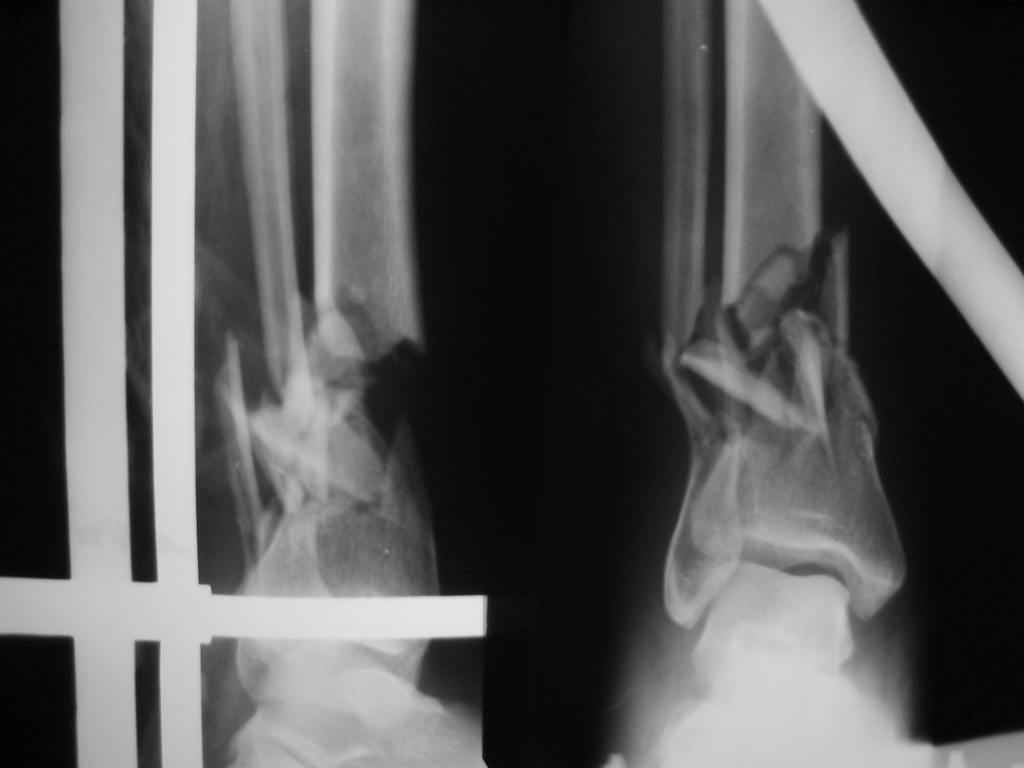

Открытый перелом (1А Каплан)у женщины 39 лет - падение плиты на голень.

Выбран вариант:ДРУ на месяц и EXPERT.С частичной нагрузкой на конечность сразу после операции. Хотелось бы услышать мнения по этому случаю.